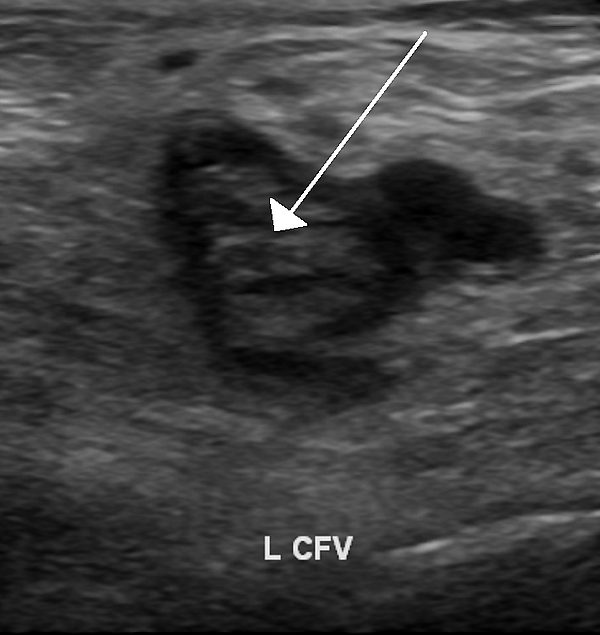

Диагностика

Понятие «состояние тромботической готовности» объединяет лабораторно выявляемую гиперкоагуляцию по так называемым «глобальным» тестам коагулограммы (тест генерации тромбина, тест тромбодинамики, тромбоэластография), увеличение содержания в крови маркеров активации гемостаза, подавление антикоагулянтной и фибринолитической активности и ряд клинических признаков предтромботического состояния[6].